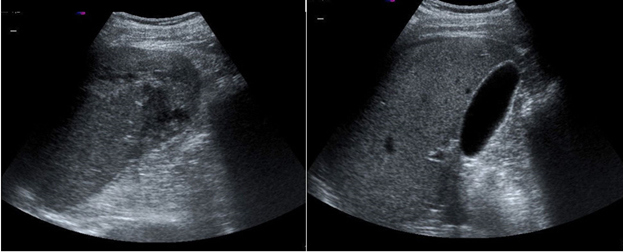

Una ecografía a pie de cama (Figura 1) en la sala de Urgencias evidencia líquido libre intraperitoneal y una masa intraesplénica heterogénea compatible con hematoma esplénico organizado, que permite el diagnóstico de esta rara patología.